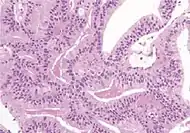

Acinar adenocarcinoma with multiple nucleoli.

Acinar adenocarcinoma with double and eccentric nucleoli.